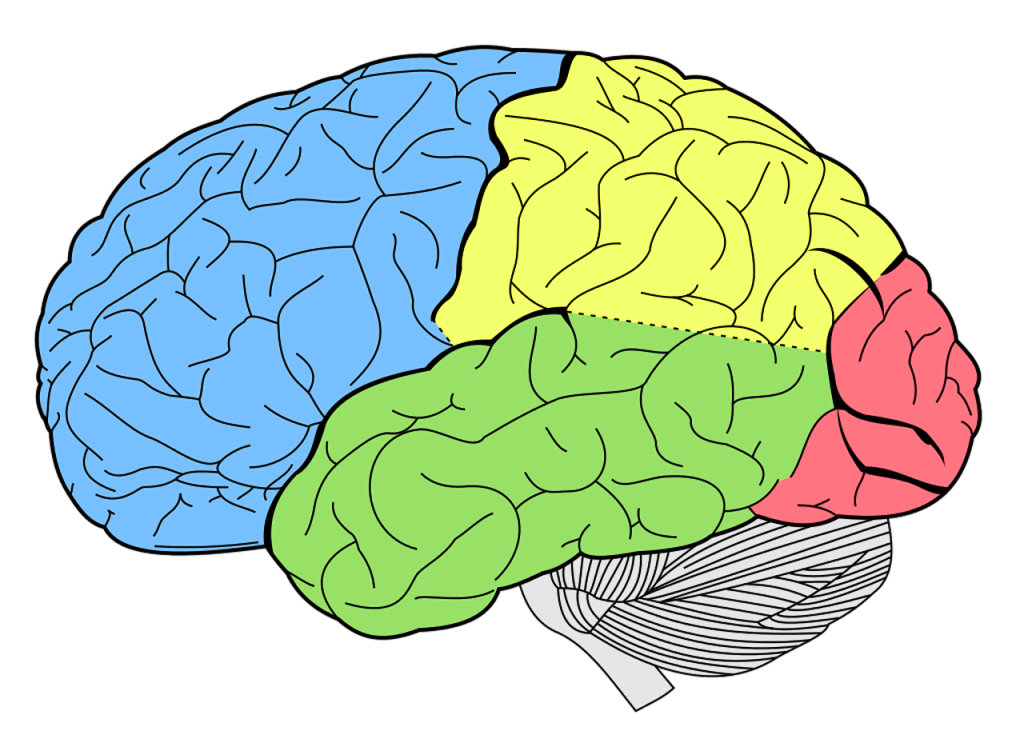

The parietal lobe is the middle part of the brain. It is located behind the central furrow towards the back. It is separated by incision preoccipitalis from the occipital lobe, lying completely posteriorly (1).

The incisura preoccipitalis cuts into the upper convexity of the brain hemispheres. As a result, the gyrus postcentralis, in which there are sensory centers, belongs to the parietal lobe. There are two curves in the lower area of the parietal lobes. Those are the anterior, gyrus supramarginalis and posterior, gyrus angularis.

As already said, the parietal lobe occupies the upper side of the hemisphere. The parietal lobe limits from the anterior and lateral sides include the area from the front to the central sulcus, from the temporal floor to the lateral sulcus, from the occipital sulcus to the imaginary line that flows from the upper edge of the parietal occipital sulcus to the lower hemisphere edge.

The parietal lobe, like the frontal lobe, forms a significant part of the cerebral hemisphere. In the phylogenetic relationship, it distinguishes the old part - posterior central gyrus, the new part – the upper dark gyrus, and the newest - lower dark gyrus.

Parietal lobe syndrome implies an outbreak of function of this lobe due to damage to its structures. This lobe is located between the frontal lobes in both cerebral hemispheres. The parietal lobe extends from the central sulcus to the parieto-occipital groove separating it from the occipital lobe. It contains the primary somatosensory cortex.

In the parietal lobe of the dominant hemisphere, the supramarginal and angular gyruses form part of the Wernike Speech Center. The fasciculus archuatus fibers connect the Broca’s and Wernike’s speech centers by passing through this lobe.

在优势半球的顶叶中,上三角和角回构成了韦尼克(Wernike)语言中枢的一部分。弓状束纤维通过该叶连接布罗卡和韦尔尼克的语言中枢。

The parietal lobe of the dominant hemisphere is responsible for the ability to calculate (2), as well as the left-to-right orientation. In this lobe, body schemes are found.

In the depth of the parietal lobe of both hemispheres are found fibers of optical radiation. Disorders of the parietal lobe function can result from trauma, tumors, infection, vascular events, etc. Damage caused by trauma or by another etiological factor can impair the function of the frontal lobe as well as cause frontal lobe syndrome.